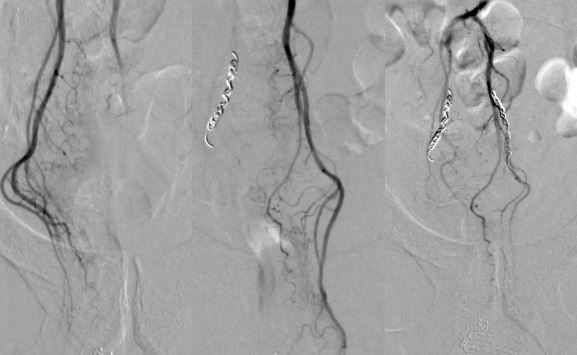

• Эндоваскулярная эмболизация верхних прямокишечных артерий — высокотехнологичная процедура, выполненная нашим рентгенэндоваскулярным хирургом. Через пункцию артерии в локтевом сгибе под рентген-контролем в питающие проблемную зону артерии прямой кишки были введены микрочастицы, чтобы дополнительно «выключить» кровоток в этой области. Это был радикальный шаг для создания гарантированного гемостаза.